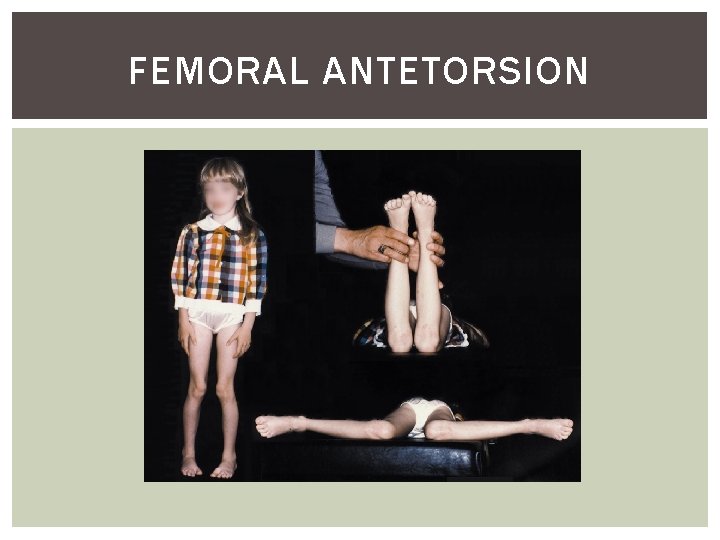

IN-TOEING GAIT Clinical assessment: Check symmetry Femoral anteversion/Medial tibial torsion/Metatarsus adducutus Natural progression: Femoral anteversion; normally self limiting by 8 years

FEMORAL ANTETORSION